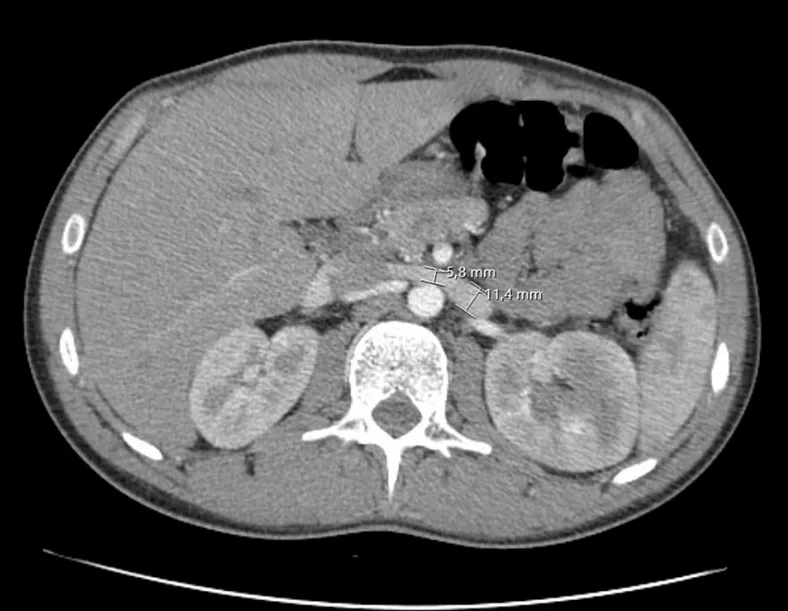

IRA + Icterícia: Um Caso que Exige Investigação Detalhada

IRA + Icterícia: Um Caso que Exige Investigação Detalhada